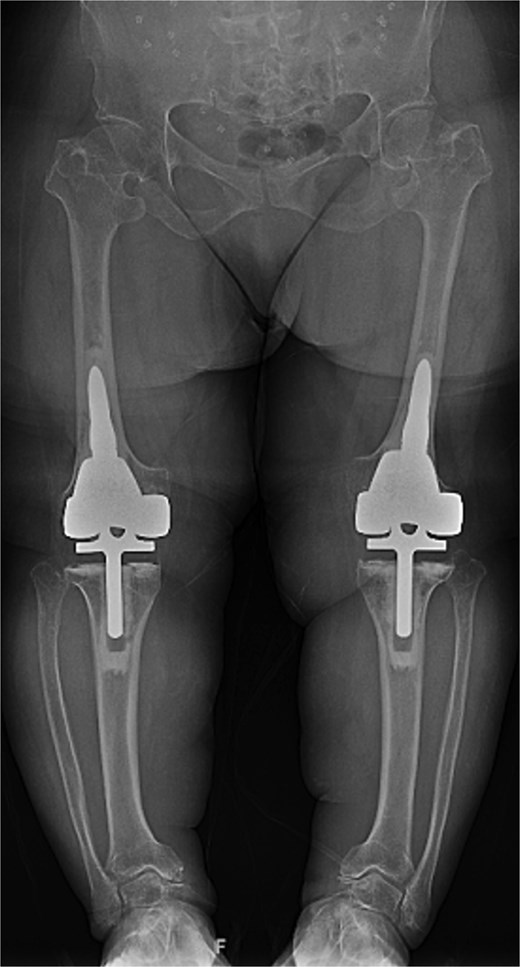

Given the severity of the coronal deformity, ligamentous laxity, and the patient’s functional limitations, the decision was made to proceed with simultaneous bilateral robot-assisted TKA using constrained prostheses. Using robotic-assisted navigation (Stryker Mako™), bony landmarks and soft tissue gaps were registered on the right knee. Initial preparation for a posterior-stabilized implant demonstrated profound lateral laxity after medial releases, prompting intraoperative conversion to a rotating-hinge design. A size XS femoral component and pediatric all-polyethylene tibial component (8 mm) were cemented, followed by hinge assembly. A similar approach was used for the left knee as severe medial compartment collapse and lateral laxity again necessitated the use of a rotating-hinge construct. The femur was prepared for an extra-small femoral component with a 12 × 50 mm cemented stem, and a size 8 mm pediatric all-polyethylene tibial component was implanted. The post-operative mechanical axis for the left and right knees were 4 and 6 degrees, respectively (Fig. 2).

Immediate postoperative AP radiographs following bilateral robot-assisted rotating-hinge TKA, showing well-aligned prosthetic components and correction of the coronal deformity. The post-operative mechanical axis for the left and right knees were 4 and 6 degrees, respectively.